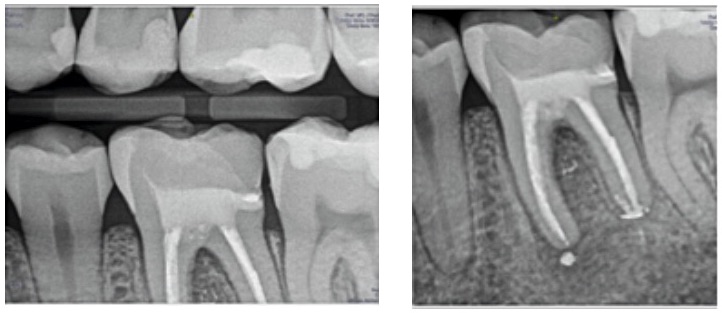

Fig. 2. Radiografía de aleta de mordida y periapical inicial.

Paciente de 27 años de edad que acude a la consulta para salvar un diente. En el examen clínico presenta dolor a la percusión.

Diagnosticamos una periodontitis apical sintomática con un tratamiento de conductos previo. Se decidió realizar la reendodoncia del diente 3.6. y proceder a su restauración definitiva.

Fig. 7. Radiografía final del retratamiento no quirúrgico del 3.6. con su restauración indirecta cementada.